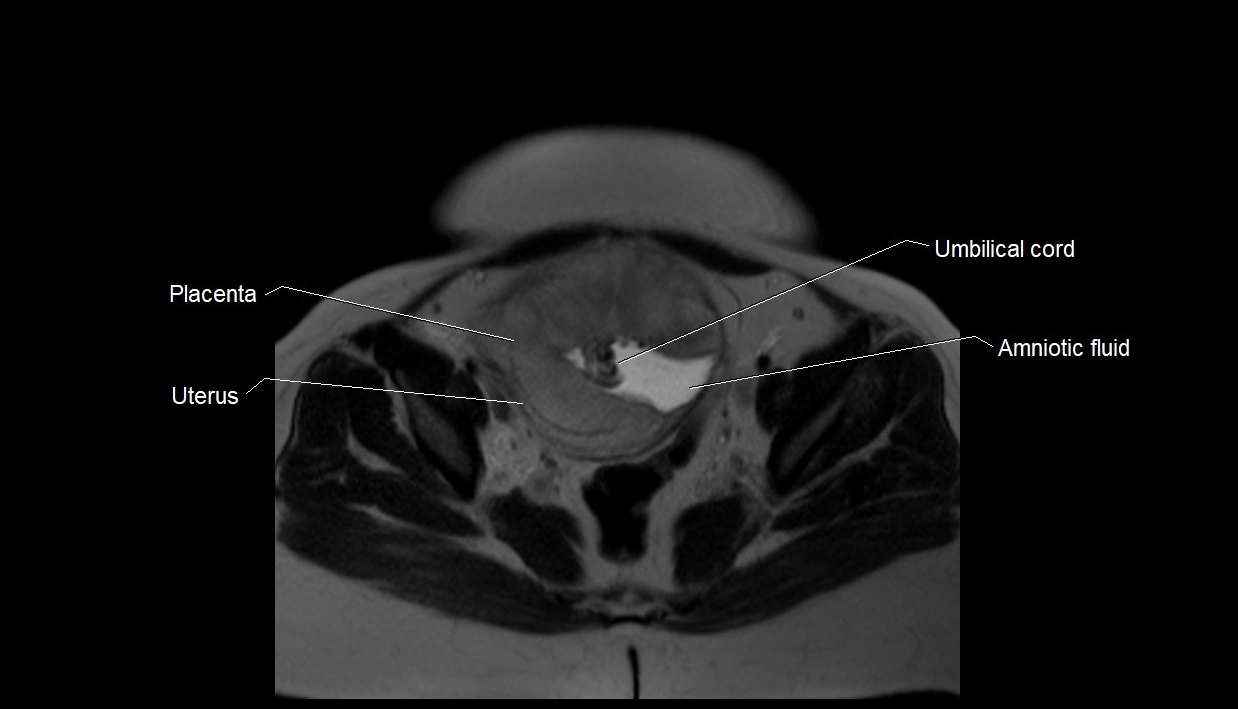

MRI Appearance

T2 HASTE (T2 GRE):

• Amniotic fluid shows very bright hyperintense signal

• Provides natural contrast against fetus and placenta

• Small particles (vernix) may appear as scattered hypointense foci within bright fluid

T1 GRE:

• Amniotic fluid shows low signal intensity (dark)

• Hemorrhage, infection, or proteinaceous content may cause focal or diffuse high signal intensity

MRI image

image